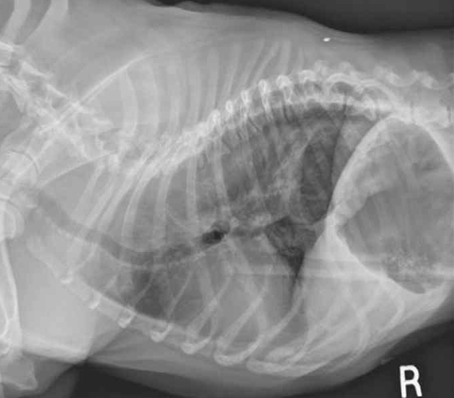

- Plain radiographs : X-ray로 쉽게 진단 가능.

| Plain | Contrast (*Sliding) |